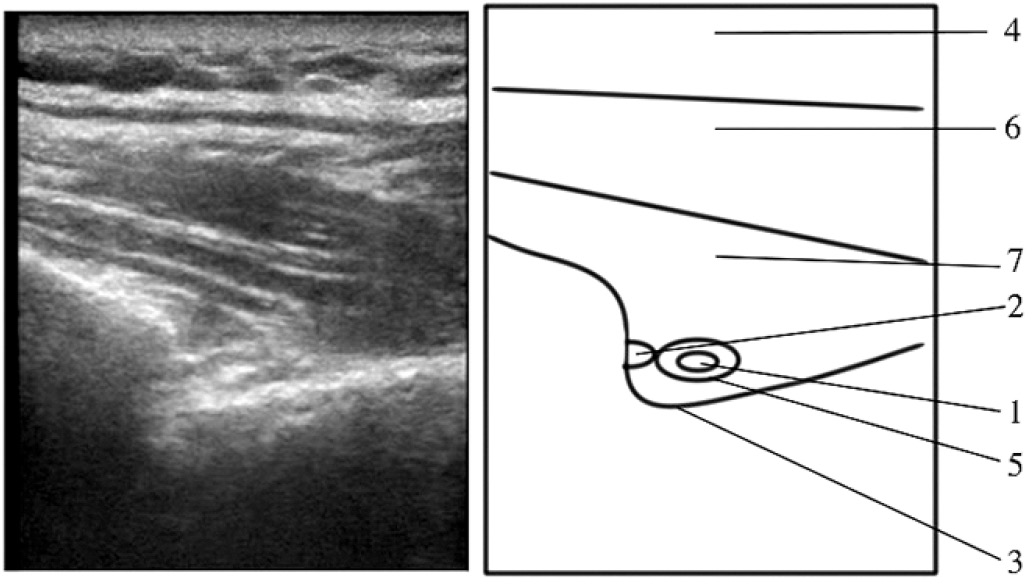

Пациент в положении лёжа на здоровом боку, оперируемая конечность сверху, плечо приведено, лежит свободно вдоль тела. УЗ-сканирование проводили в области надостной ямки лопатки, смещая датчик до визуализации вырезки лопатки, после чего датчик возвращали в исходное положение. Иглу вводили медиальнее датчика, подводя её кончик к надлопаточному нерву, ориентируясь на пульсацию надлопаточной артерии (анэхогенная, пульсирующая, несжимаемая, округлая структура) (рис. 3, 4). Для блокады надлопаточного нерва инъецировали 5 мл 0,75% раствора ропивакаина.

Рис. 4. Оценка ретроградного распространения раствора местного анестетика – плоскость сканирования над вырезкой лопатки: 1 – надлопаточный нерв, 2 – надлопаточная артерия, 3 – вырезка лопатки, 4 – подкожная клетчатка, 5 – гипоэхогенная тень – местный анестетик периневрально, 6 – трапециевидная мышца, 7 – надостная мышца